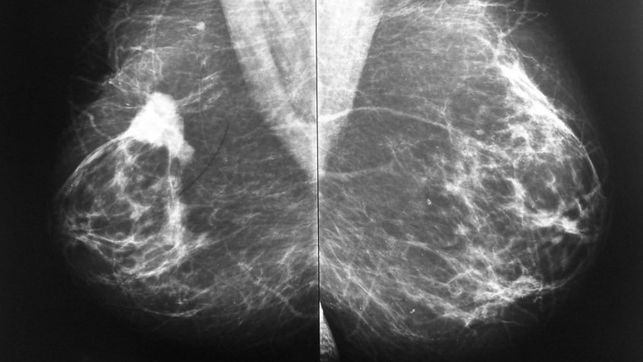

[17] El negocio de especular con el cáncer, por Juan Luis Sánchez

[29] El negocio de especular con el cáncer, por Juan Luis Sánchez